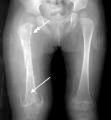

Koch's hip mortar & pestle type

Koch's hip mortar & pestle type xray2